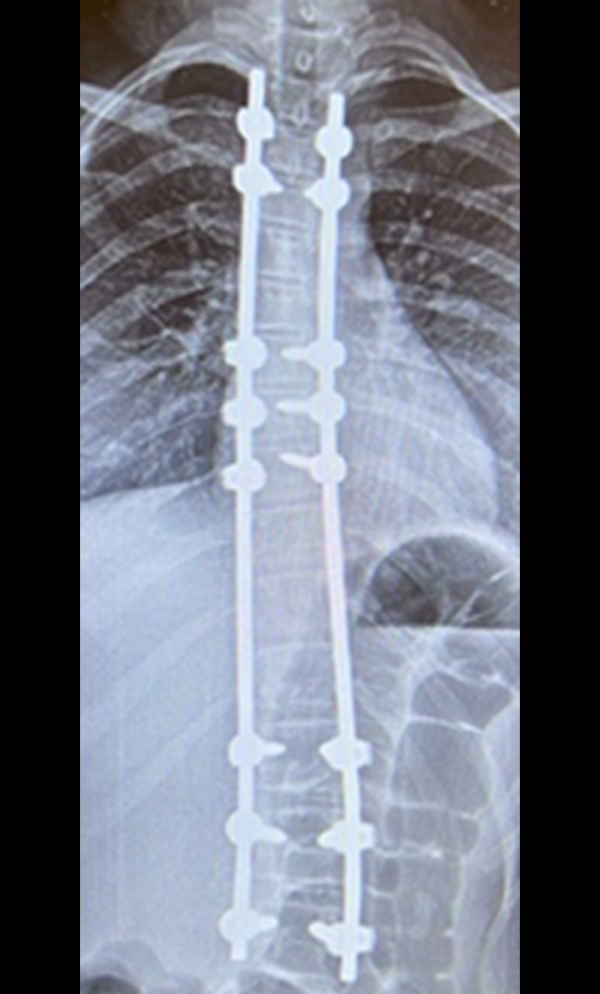

Gallery : Before - After